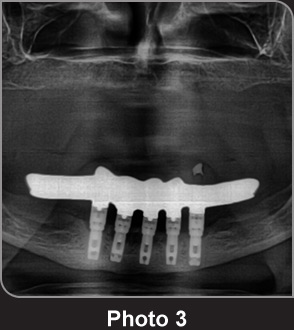

上顎金屬種植支架的OPG圖片。